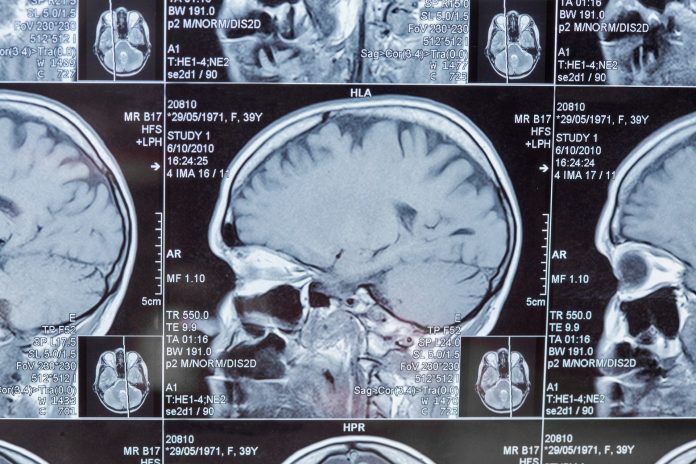

A new study has found that older adults who suffer a traumatic brain injury (TBI) are more likely to develop dementia, need home care, or be admitted to long-term care.

Traumatic brain injuries happen when someone hits their head or experiences a strong force, such as in a fall or car accident.

It can lead to confusion, memory loss, slurred speech, or weakness in the body. In older adults, more than half of these injuries are caused by falls, which are often preventable.